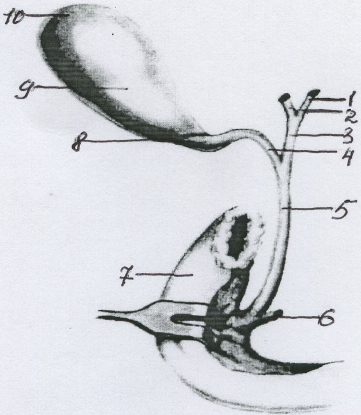

Анатомия и особенности Гартманова кармана желчного пузыря